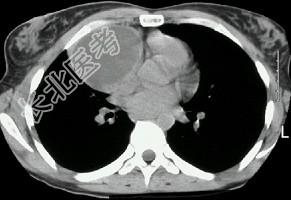

- 单项选择题女,18岁, 自感胸闷,X光检查见纵隔占位, CT检查如图,最可能的诊断为 ( )